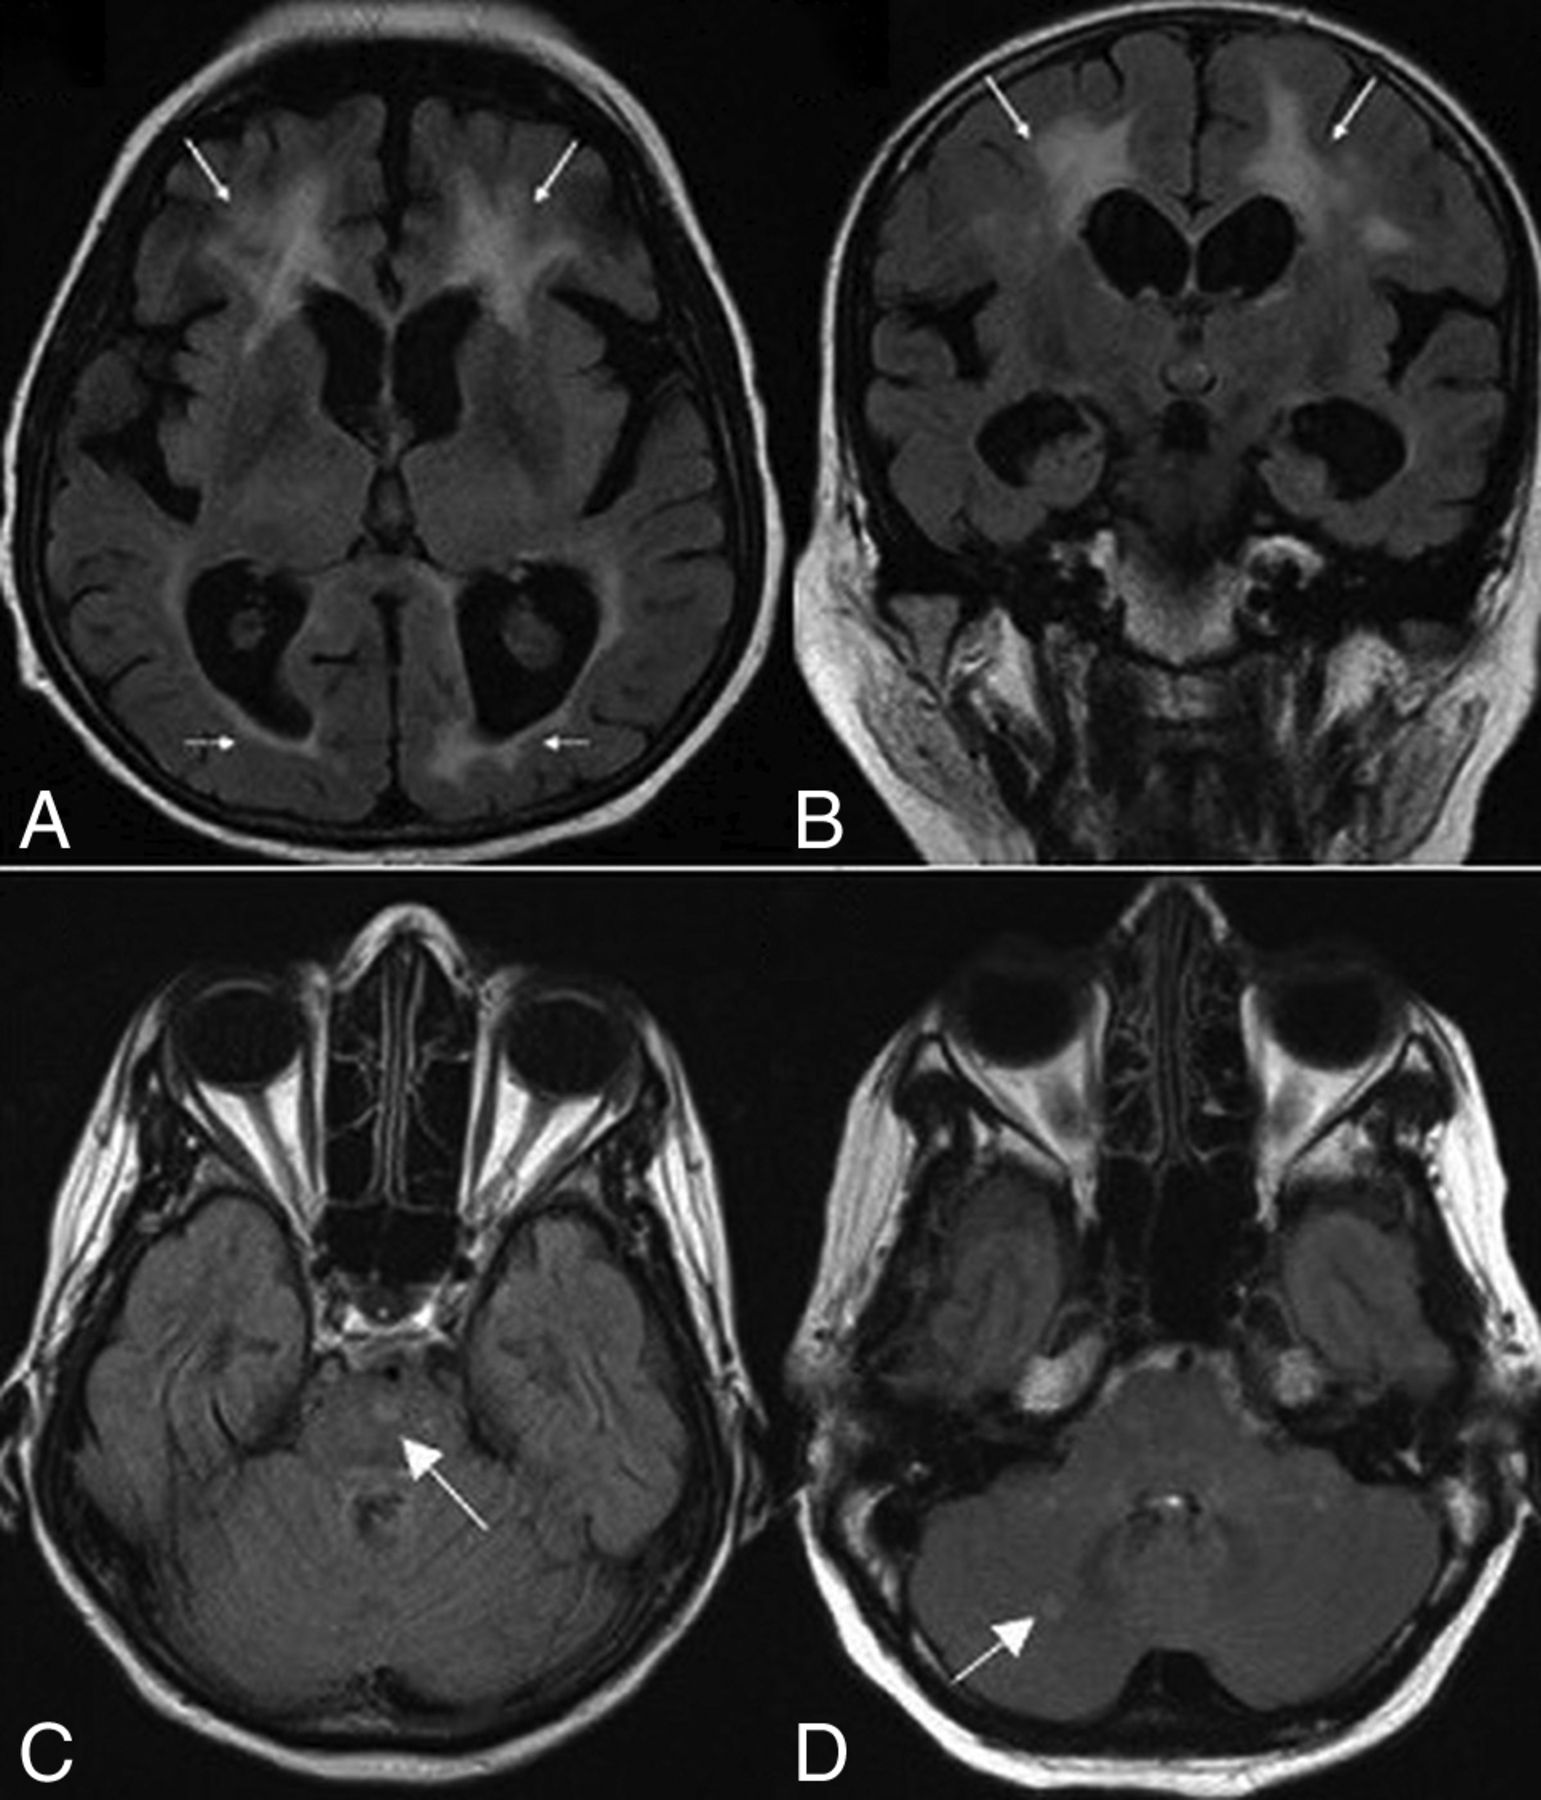

Evidence of iron deposition in the globus pallidus was observed in 19 patients (73%) (Fig 2A–C). Involvement of the substantia nigra and red nucleus was noted in 6 patients (23%) (Fig 2D). MR spectroscopy in 4 patients demonstrated normal major metabolite peaks. Despite the clinical finding of generalized or focal dystonia, 3 patients showed no evidence of iron deposition on MR imaging.

Axial T2-weighted (A), FLAIR (B), and T2* (C) MR images in case 11 show putaminal blooming artifacts (arrows) reflecting iron accumulation. An axial T2* MR image (D) in case 3 shows iron deposition in the substantia nigra (arrowheads).

White matter abnormalities on T2-weighted and FLAIR images were seen in 18 patients (69.2%). These changes varied in terms of distribution and extension (Fig 3). Extension of WM changes was characterized by a periventricular and frontoparietal predominance (Fig 4A, -B). Involvement of other subcortical (basal ganglia, thalamus) and infratentorial structures was seen in 3 patients (11.5%) (Fig 4C, -D). Older age was associated with more severe white matter lesions (r = 0.71, P < .001). All white matter lesions were nonenhancing and spared the U-fibers.

Axial (A) and coronal (B) FLAIR MR images for case 24 show white matter changes with frontal predominance (arrows). Axial FLAIR images show signal intensities (arrows) involving the pons (C) in patient 19 and the cerebellum (D) in patient 26.